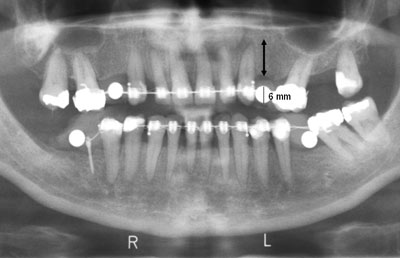

På et panoramabillede bør morfologi og struktur (kvalitet) af kæbeknoglen vurderes systematisk, og patientens højre og venstre side skal sammenlignes direkte. Højden af den marginale knogle i tandløse områder kan almindeligvis bedømmes på panoramabilledet, når der tages højde for billedets forstørrelsesgrad, som bedst vurderes ud fra en indeksponeret metalmarkør med kendt dimension placeret i det/de aktuelle område(r) (Fig. 10). Denne fremgangsmåde er især relevant i forbindelse med implantatbehandlingsplanlægning. Panoramabilledet kan ikke anvendes til vurdering af den facio-orale udstrækning af kæbeknoglen, men kan give oplysninger om evt. nabotænders hældning i horisontalplanet og dermed give en rettesnor for den horisontale vinkling af planlagte implantater.

Fig. 10. Beskåret panoramabillede med indeksponerede metalindikatorer (5 mm kugler) for bedømmelse af billedets forstørrelsesgrad i alle kæbekvadranter. En udmålt kuglediameter på 6 mm indikerer en forstørrelsesfaktor på 1,2 (20 %). Knoglemålet markeret med pil skal korrigeres for denne forstørrelsesfaktor.